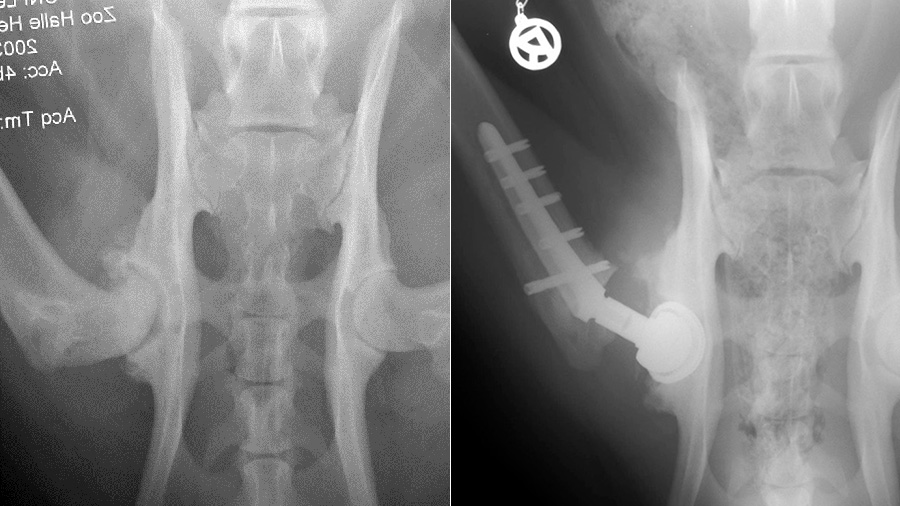

The Leipzig Zoo tiger named Girl—one of just 500 Malaysian tigers in existence in 2011 when the surgery took place—was clearly suffering: She had been experiencing right hip lameness for more than a year and was down to just 93 kg—from a normal weight of around 130 kg. Prof. Dr Peter Böttcher, associate professor at the University of Leipzig, evaluated her with X-rays and computed tomography (CT) scans and immediately called in the experts: a producer of a cementless hip prosthesis for dogs, and Cremona, Italy-based Dr Aldo Vezzoni, the most experienced surgeon in canine cementless hip prosthesis. The producer and Vezzoni collaborated to create a custom hip prosthesis to be implanted in Girl.

“Human implants were too big because a human is a biped animal, with bigger hip joints,” said Vezzoni. He settled on a mix of custom-made implants designed for humans and also suitable for large dog breeds like Neopolitan Mastiffs, Caucasian Shepherds, Great Danes and Saint Bernards: 34, 36 and 38 mm prosthetic hip cups, a 12 mm stem, 5 mm diameter locking screws, a 26 mm aspherical head with aspherical diamond coating, and a dedicated jig and reamers.

The surgery took place January 23, 2011 at the University of Leipzig School of Veterinary Medicine and Girl could not have been in better hands: In the operating room with Vezzoni were Böttcher, anesthetist Prof. Michaele Alef, and assistants Dr Ilka Joop, Slobodan Tepic, Dr Hinnerk Werner and Leipzig Zoo veterinarian Dr Jens Thielebein.